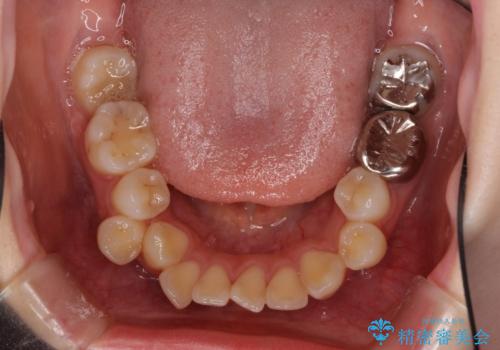

- 口元の突出感を気にして来院された患者様です。

上下左右の第一小臼歯4本を抜歯して口元を下げる治療計画としました。